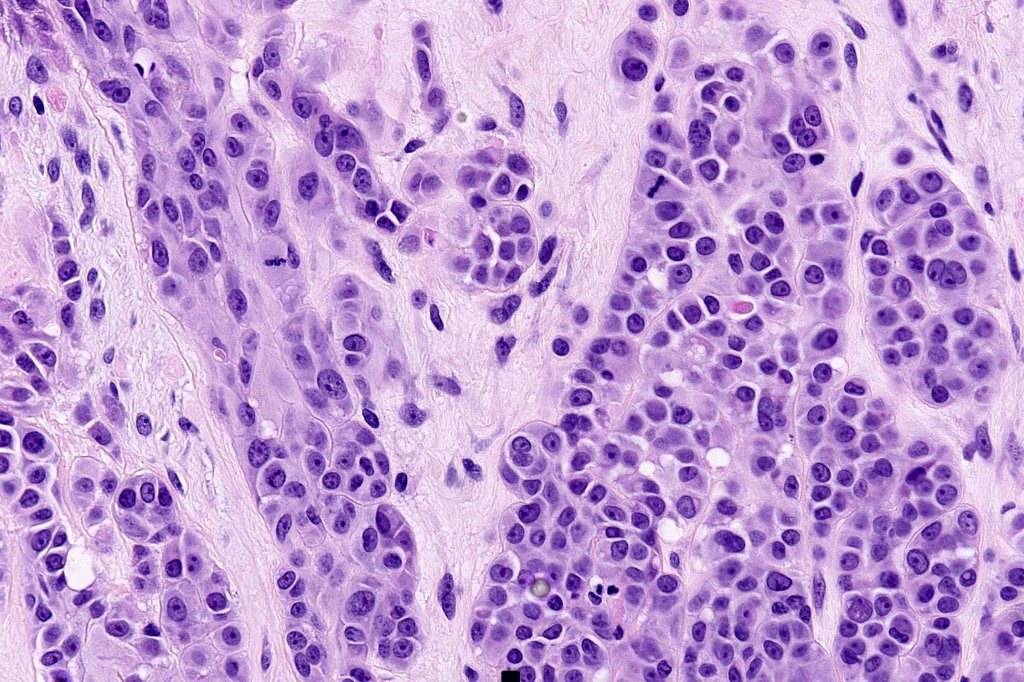

Histological features

•>5-10 mm

•Involve deep dermis or subcutis

•Asymmetrical, poorly circumscribed

•May show effacement/consumption of epidermis or ulceration

•Peripheral Pagetoid spread

•Large nodules which often show impaired maturation

•Loss of gradient with HMB45 and Ki67

•>20% Ki67 expression

•TERT promoter & PTEN mutations

•DNA copy-number variations